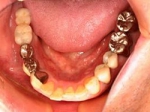

術前口腔内写真

術後口腔内写真、食事がおいしくなったと非常に満足されている。